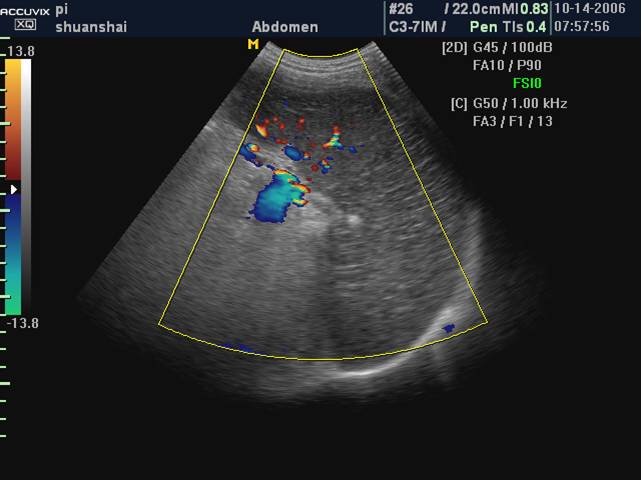

彩色多普勒

无血流信号

超声造影

无增强